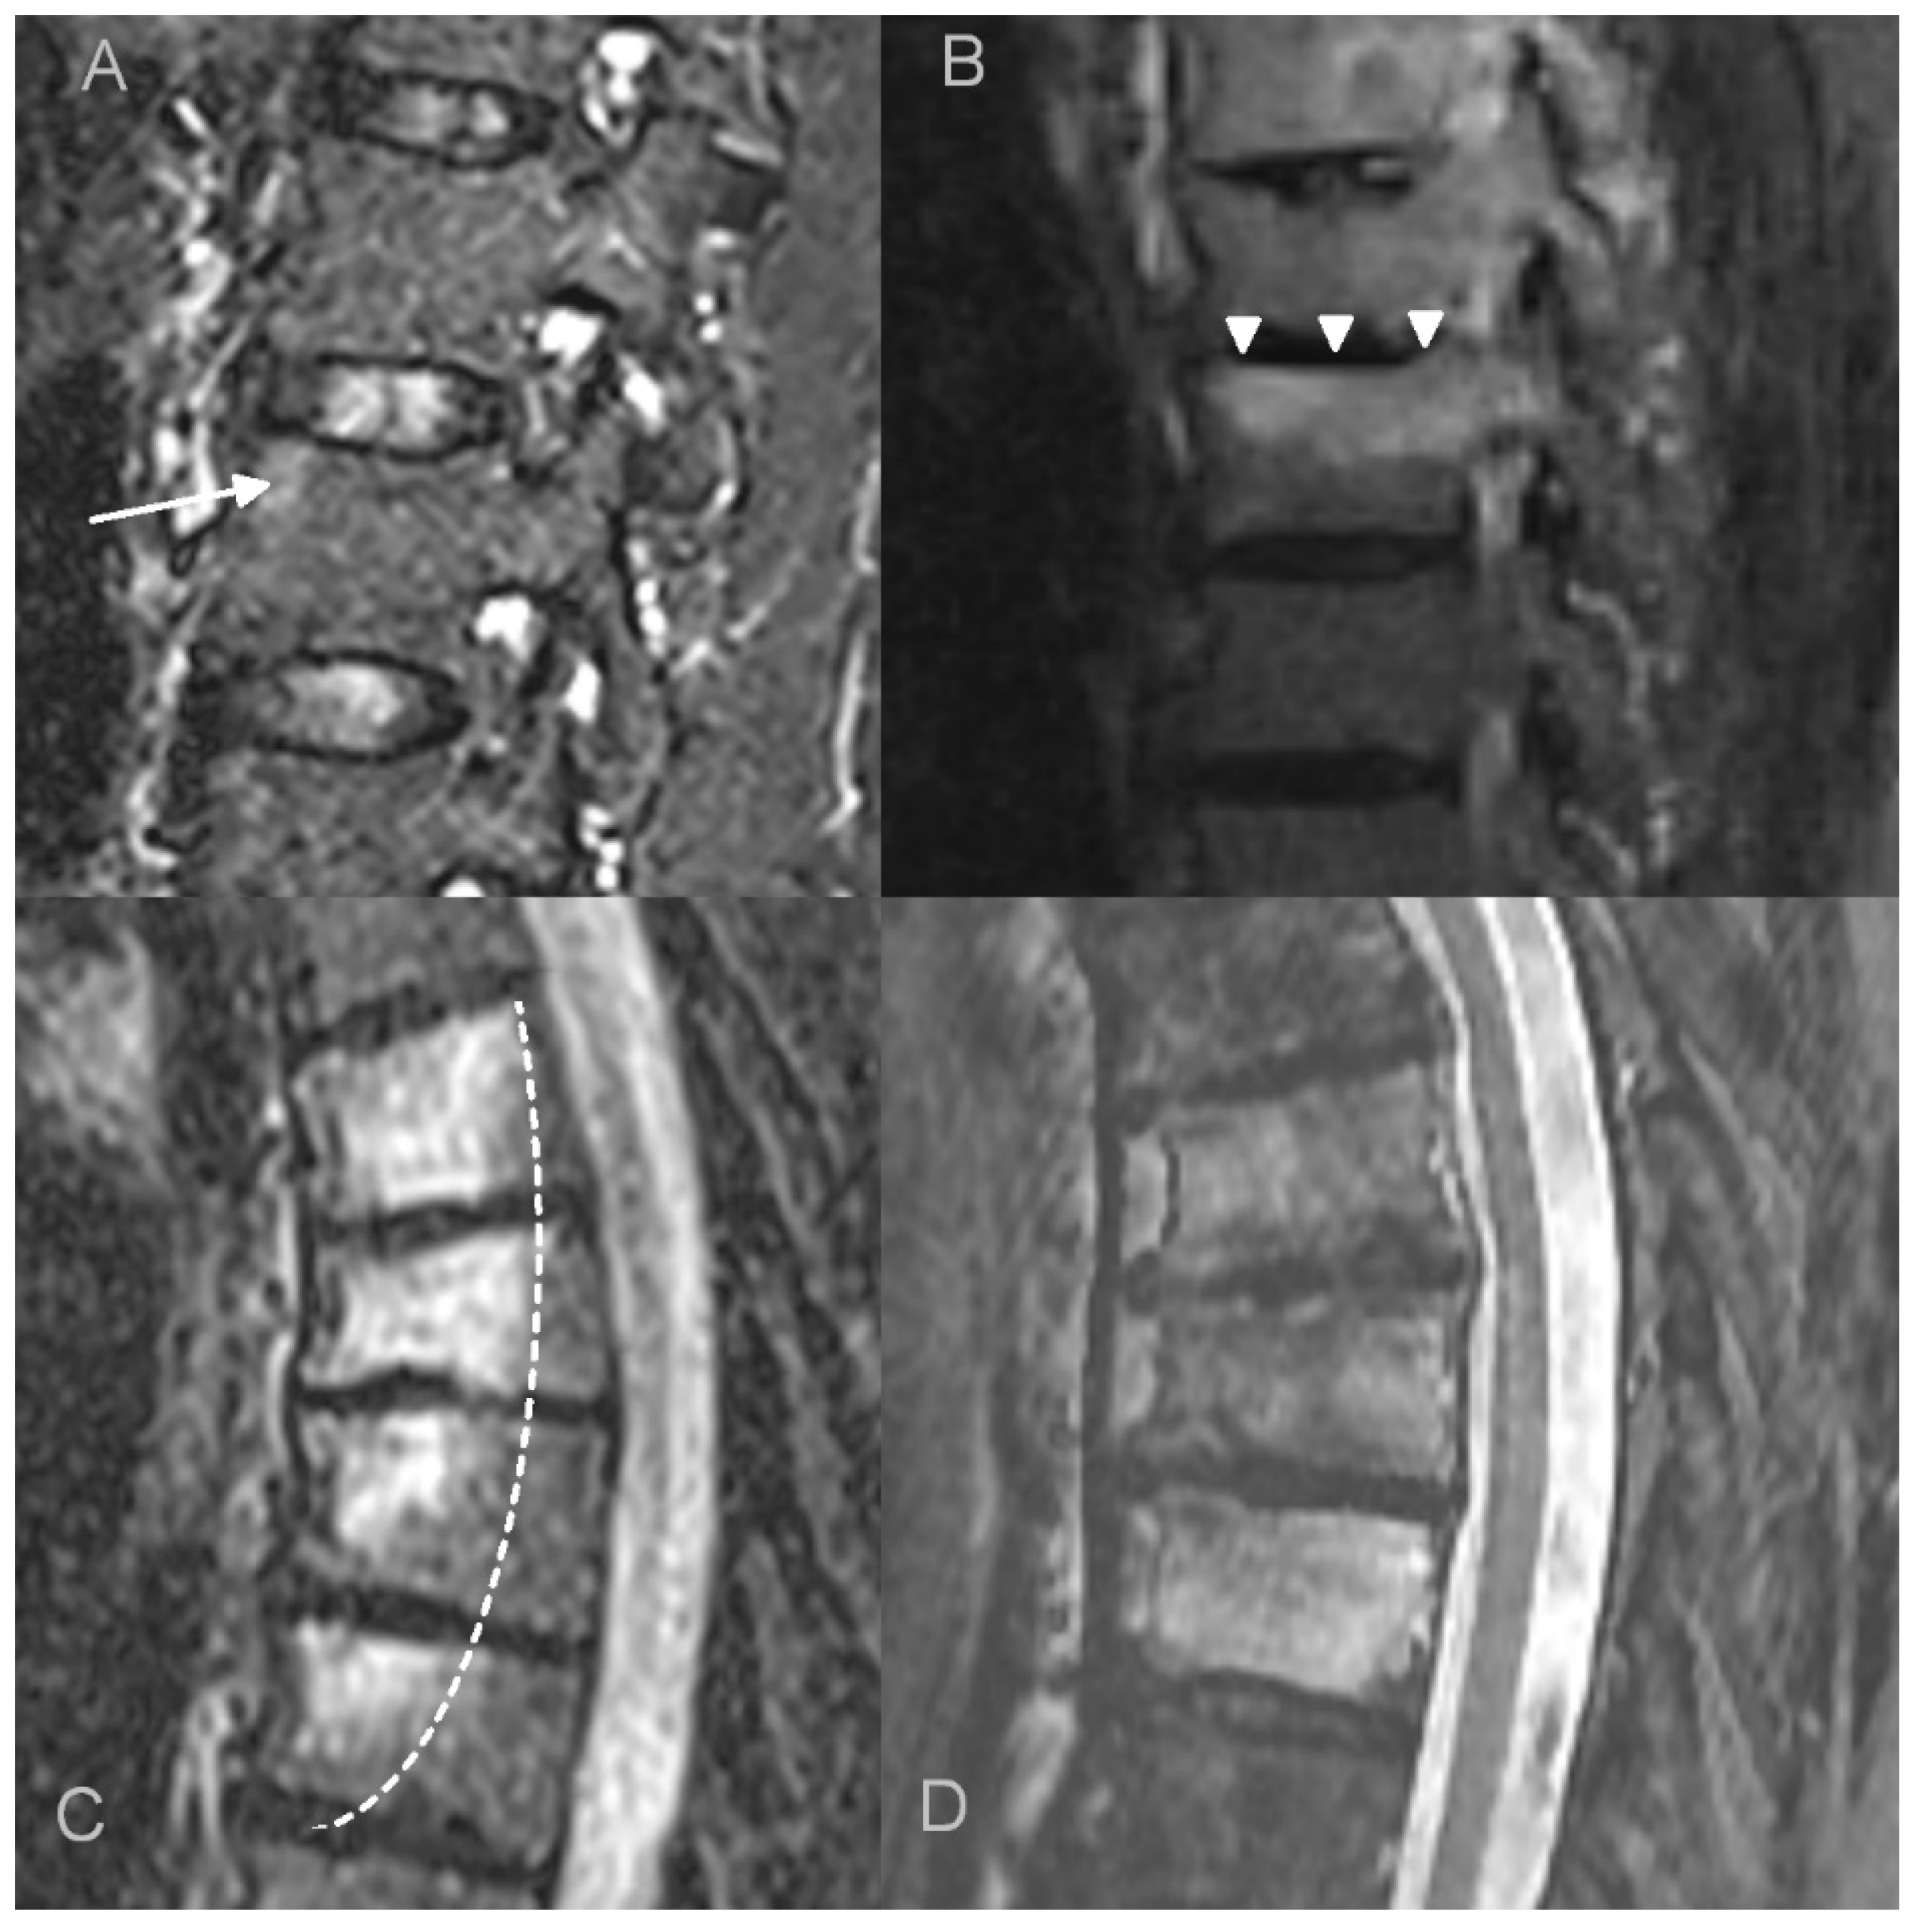

In adults, the main findings were BME, osteosclerosis, endplate irregularities, and a spectrum of ankylosing lesions. Similar to previous publications, the lesions were multilevel and contiguous [21,22,32,33]. Curvilinear/semicircular pattern of BME found in the majority of patients in the study by McGvuran and coworkers was less common in our material three patients); however, both BME and osteosclerosis overlapping BME on plain film/CT were definitely the most striking abnormalities (Figure 4) [22]. We also observed a long persistence of BME that was present through the whole length of follow up, even in patients followed for more than 10 years. On MRI, contrast enhancement was observed in the areas of BME, but also in the linear fashion along the endplates and frequently in the non-ankylosed costovertebral and facet joints. Paraspinal soft tissue involvement was observed in 10 out of 12 patients subjected to MRI (83%), more often than in previous publications [22,34]. In agreement with previous reports, most of the intervertebral discs showed decreased T2 signal corresponding to degeneration rather than the high signal seen in discitis [22]. Vertebral deformities were limited to anterior wedging, most pronounced at the apex of thoracic kyphosis. Ankylosing lesions were prevalent and, as previously reported, showed a progressive character on follow up [35,36]. Anterior bony bridging resembling this observed in diffuse idiopathic skeletal hyperostosis (DISH) was accompanied by intervertebral fusion and facet joint ankylosis. Contrary to previous reports, we have not observed the resolution of hyperostosis once ankylosis was complete [36].

Figure 4.

Imaging findings of the thoracic spine involvement in a 65-year-old patient with SAPHO syndrome. CT (A) shows multilevel, contiguous vertebral osteosclerosis, endplate erosions, and early syndesmophyte formation. MRI (B) shows diffuse and propagating patterns of BME and mild prevertebral soft tissue inflammation.